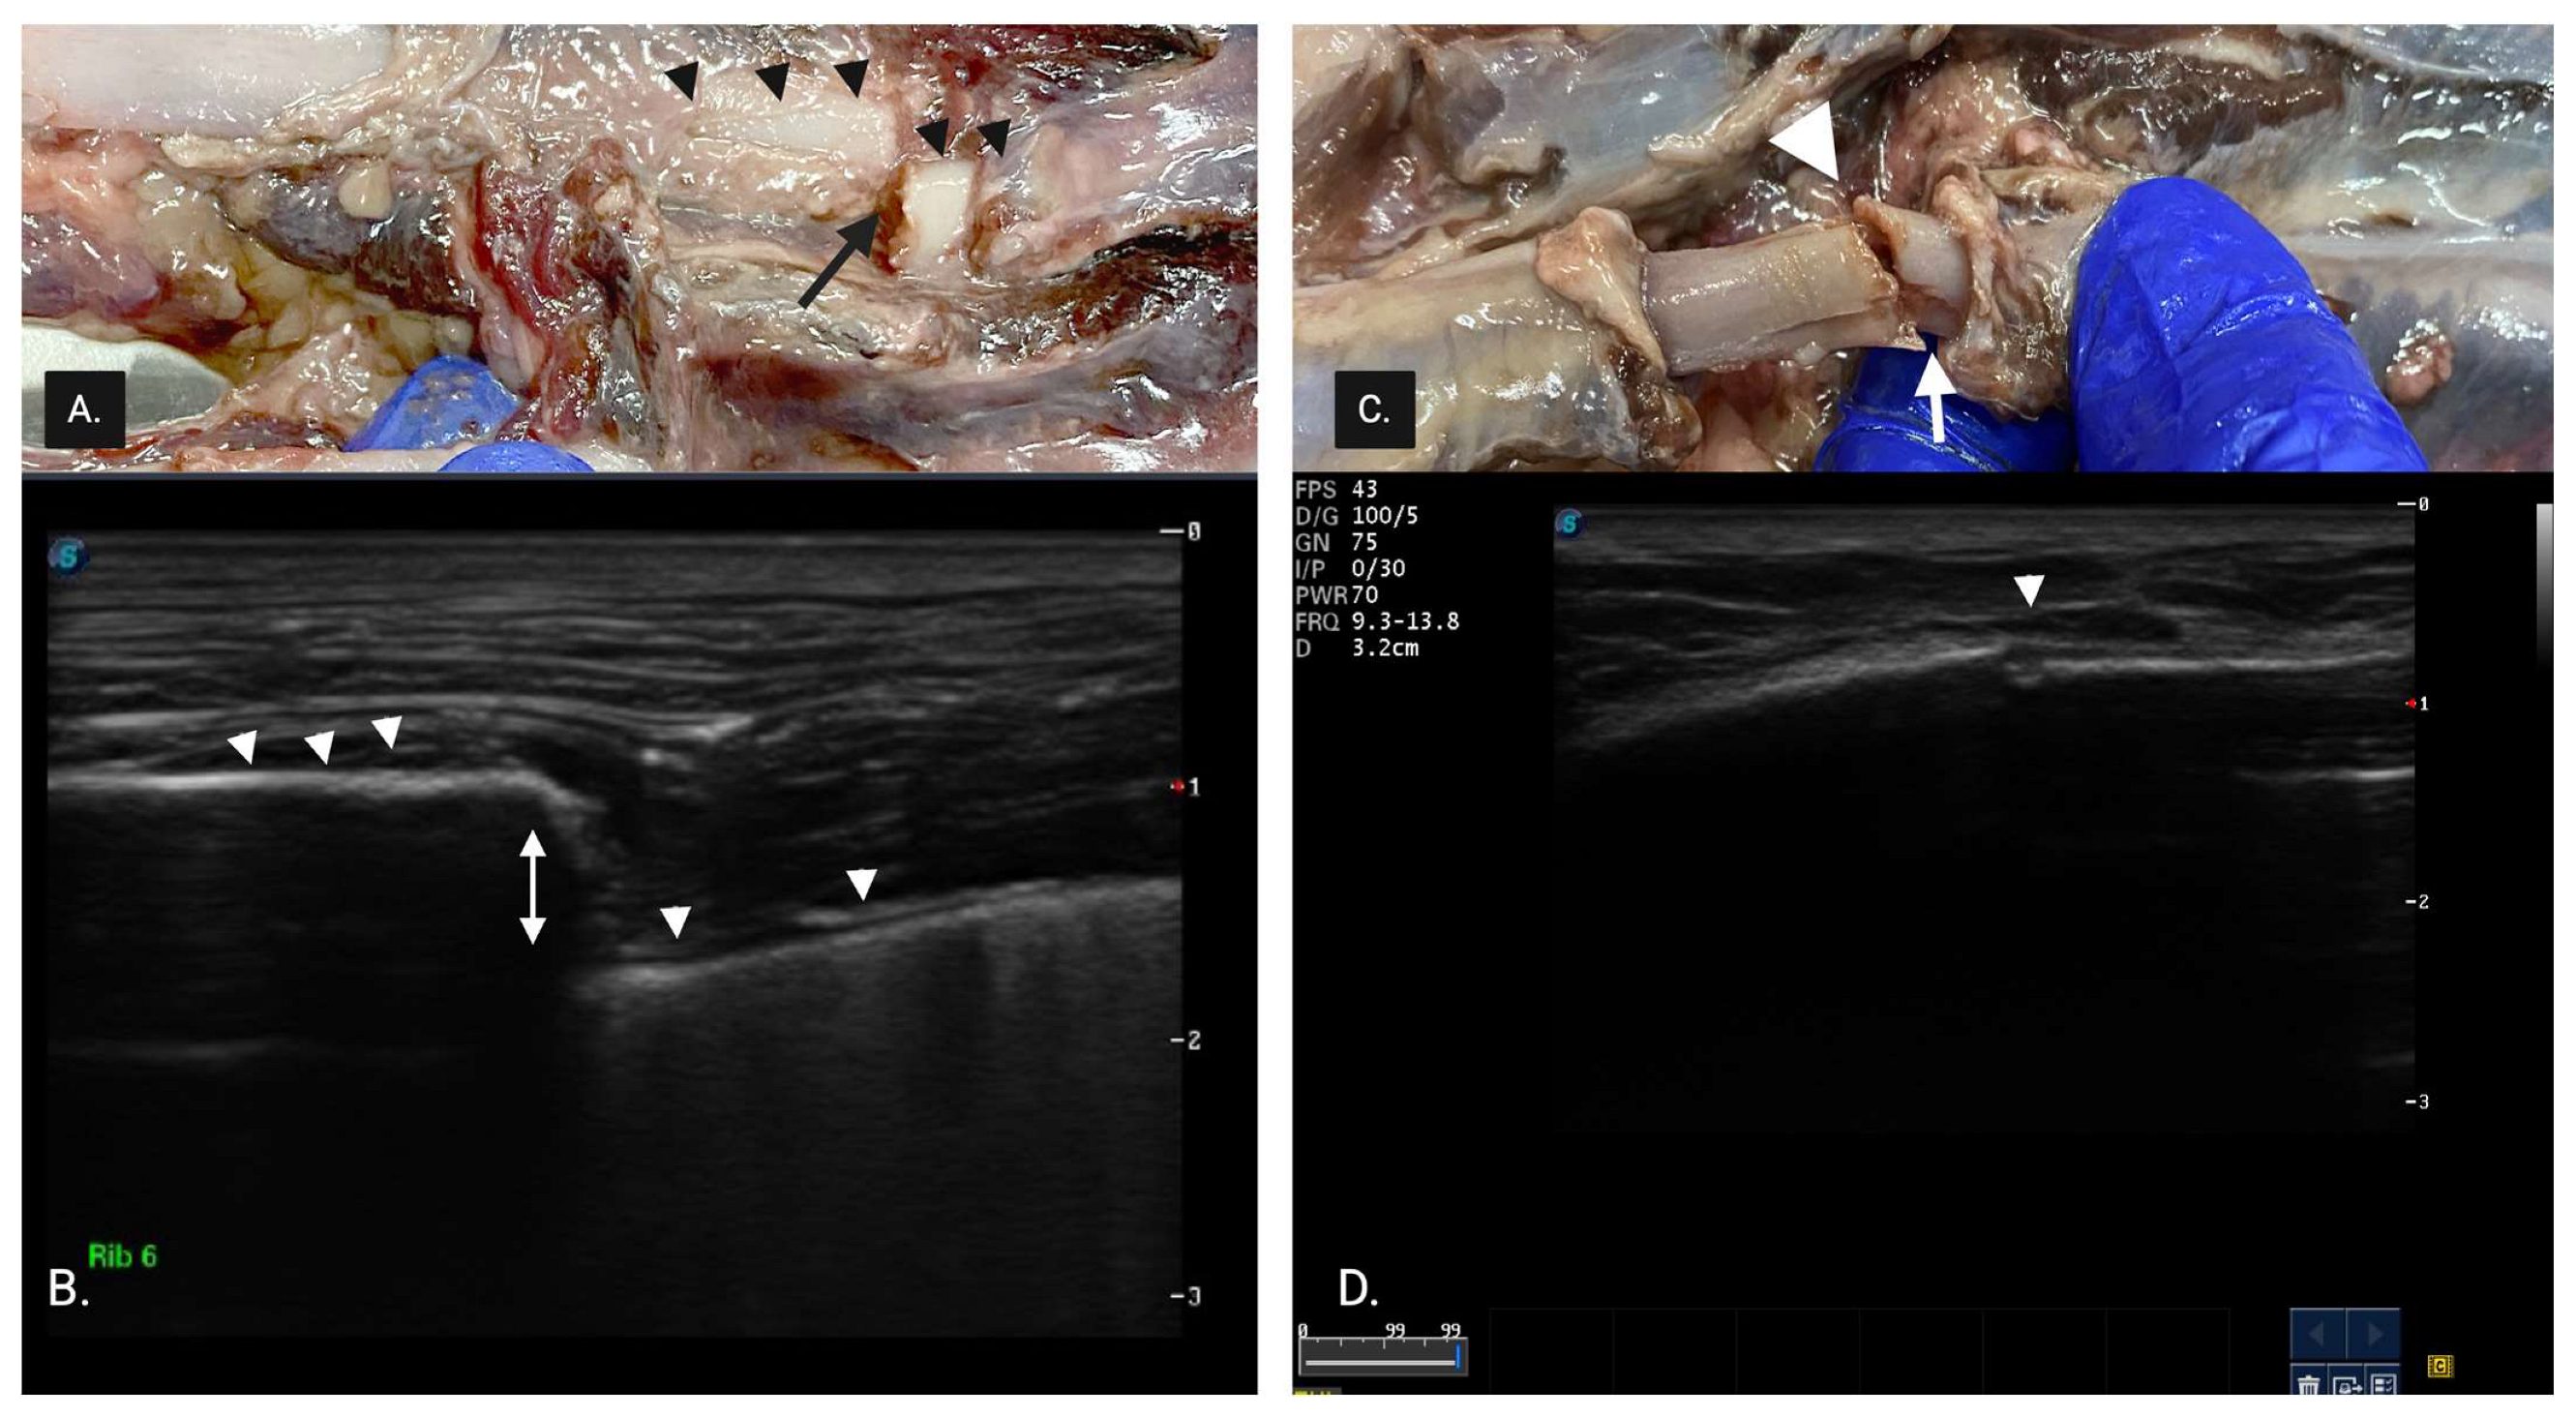

A green stick fracture (GSF) (Figure 3) was diagnosed as involving only one cortex and was further categorized into either internal greenstick (superficial cortical disruption limited to bone adjacent to the parietal pleura) or external greenstick (deep surface cortical disruption limited to bone adjacent to the muscles of the thoracic wall) whenever possible.

Figure 3.

(A) External green stick fracture seen on necropsy. The white arrowheads show the superficial surface of the cortex of the rib. The white arrow shows the discontinuity of the superficial surface of the cortex adjacent to muscles of the thoracic wall. (B) Ultrasonographic image of (A). The white arrowheads show the cortex of the rib. The white arrow shows the small divot in the hyperechoic cortical rib margin with a small loss of cortical integrity, suggesting an external green stick fracture (GSF). It involves only one cortex with superficial cortical disruption limited to bone adjacent to the intercostal muscles. (C). Internal GSF seen on necropsy. The white arrowheads show the superficial surface of the cortex of the rib. The white arrow shows the continuity of the cortex adjacent to parietal pleura. (D) Ultrasonographic image of (C). The white arrowheads show the cortex of the rib. The white arrow shows the pronounced bend in the hyperechoic cortical rib margin without a loss in the cortical integrity in the superficial bone, suggesting an internal GSF. It involves the presence of a smooth superficial cortex despite the significant degree of cortical bending.